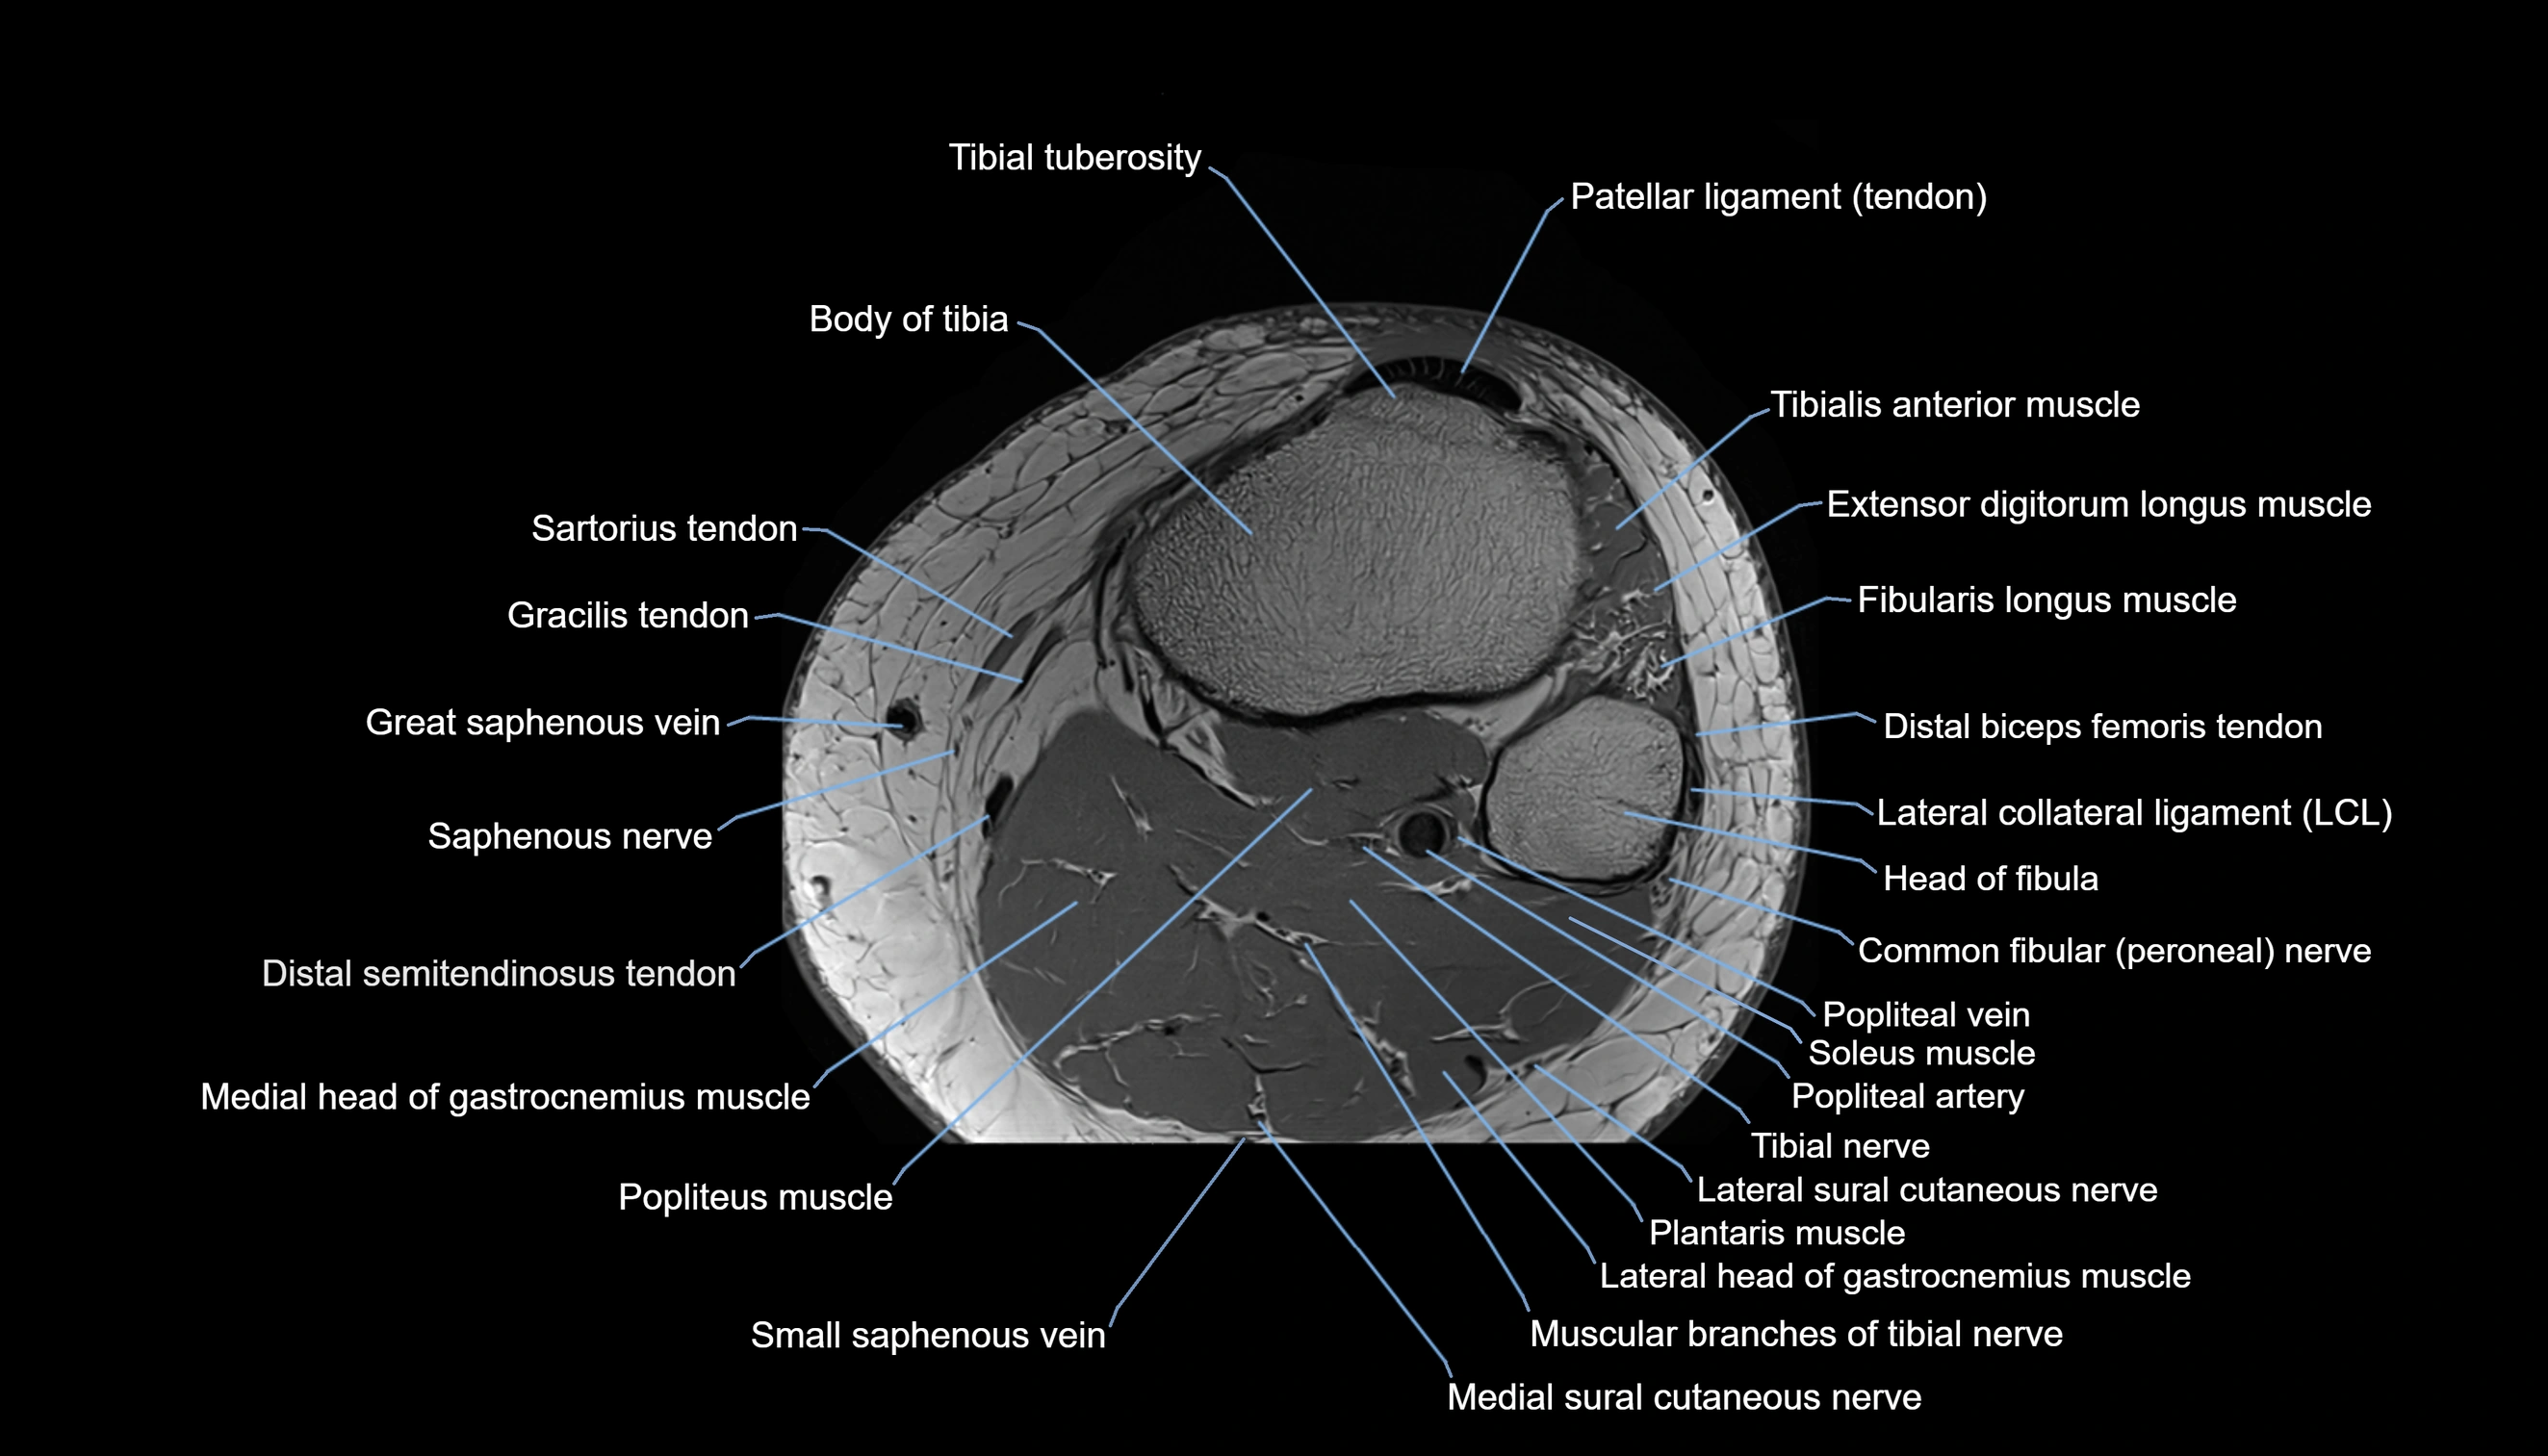

- Body of tibia

- Common fibular nerve

- Head of fibula

- Lateral collateral ligament

- Lateral head of gastrocnemius muscle

- Lateral sural cutaneous nerve

- Medial head of gastrocnemius muscle

- Medial sural cutaneous nerve

- Muscular branches of tibial nerve

- Popliteal artery

- Popliteal vein

- Popliteus muscle

- Saphenous nerve

- Sartorius muscle

- Sartorius tendon (Distal)

- Small saphenous vein

- Soleus muscle

- Tibial nerve

- Tibial tuberosity

- Tibialis anterior muscle

- Gracilis tendon (Distal)

- Distal biceps femoris tendon

- Distal semitendinosus tendon